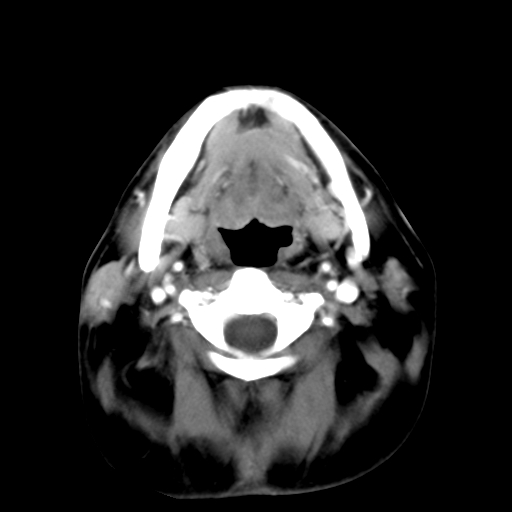

标题: CT24019:男,45岁,发现颈部肿物5个月。 [打印本页]

男,45岁,发现颈部肿物5个月,彩超示:双侧颈部及下颌部软组织增厚。

考虑双侧颈项部良性对称性脂肪增多症。